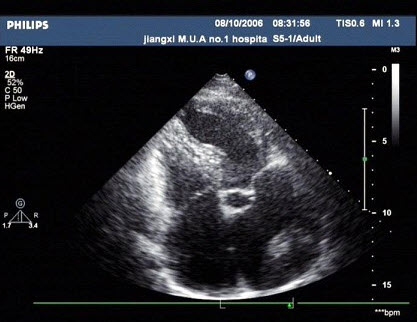

54、单项选择题

某患者左室长轴切面超声心动图如图所示,诊断为()